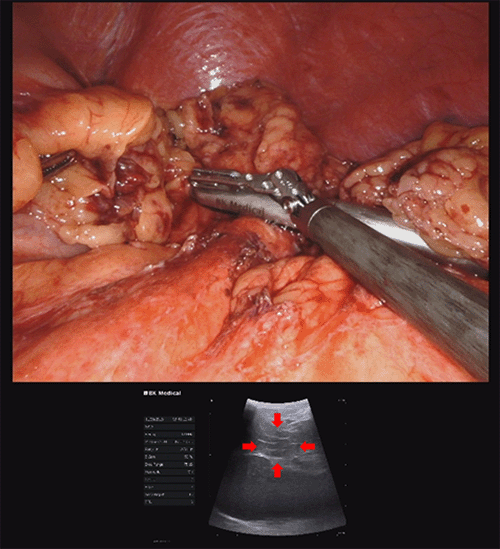

Given the absence of a definitive diagnosis and concern for a possible pancreatic neuroendocrine tumor due to the enhancement pattern and elevated chromogranin A, the patient was referred to surgical oncology. A robotic distal pancreatectomy and splenectomy with intraoperative pancreatic ultrasound were performed (Figure 3).

Figure 3. Robotic-Assisted Distal Pancreatectomy and Splenectomy with Intraoperative Ultrasound to Localize Pancreatic Lesion (Red Arrows) in Tail. Published with Permission

The patient tolerated the procedure well and was discharged on postoperative day 4 without complications. Final pathology revealed pseudocysts containing necrotic material and polarizable crystals consistent with uric acid crystals, along with focal chronic pancreatitis.